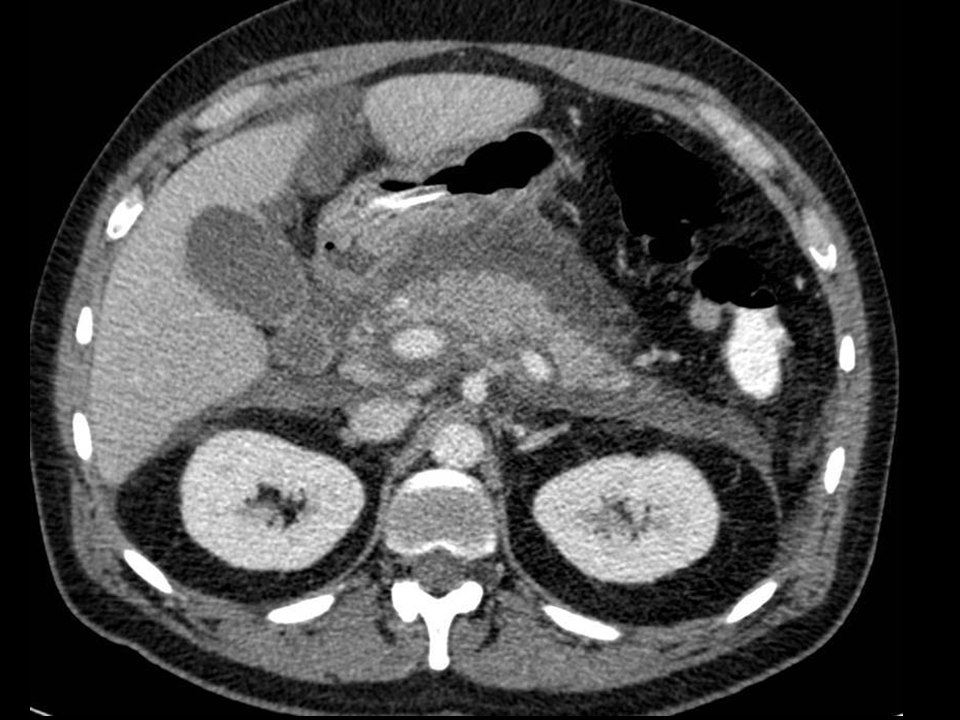

• In the periumbilical region bowel obstruction, acute pancreatitis, early appendicitis, mesenteric thrombosis/embolisation, aorta-aneurysm or diverticulitis can present with pain.

• The diagnosis of acute pancreatitis has to be based on the complex assessment of the patient. The results of all three: clinical picture, blood results (amylase value, inflammatory parameters) and imaging finding have to be considered. The positivity of at least two examinations can confirm pancreatitis. The role of diagnostic imaging therefore, is to differentiate other processes involving the periumbilical region or to assess the complications of pancreatitis. Peritoneal irritation caused by pancreatitis can create small bowel paralysis and air-fluid levels.

19. Plain abdominal X-ray, sentinel loop.

This paralytic, periumbilical bowel loop is also called sentinel-loop. If present, it can lead to the disruption of the ultrasound examination. Any gas filled intestine over the pancreatic region will cause the hyperreflection of the sound waves, thus leaving the middle portion of the retroperitoneum obscured to sonography. If the pancreatic region is still visible with ultrasonography, the pancreas appears widened; its structure shows edematous infiltration. Free fluid is usually detectable in the peripancreatic region, the omental bursa or in other cases there is a diffuse appearance of free fluid in the whole abdomen. CT examination can identify the early phase of acute pancreatitis. In the early, edematous phase the pancreas is widened and the peripancreatic fat appears hyperdense due to the edematous infiltration. Still, the main role of CT scanning remains the assessment of the early and late complications of pancreatitis. Edema, hemorrhage and necrosis each show typical features with CT, which help in the differential diagnostics.

20. Acute pancreatitis. CT examination reveals peripancreatic fluid collection in the anterior pararenal space. The pancreas is edematous.